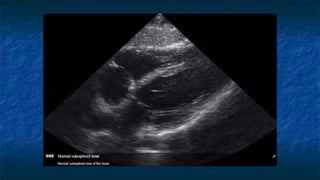

FAST: Subxiphoid exam

 Normal Anatomy

 Liver at very top of screen

 Epicardial fat vs. effusion

 Thin layer anterior to

RV

 Not present posterior

to LV

Normal Subxiphoid exam